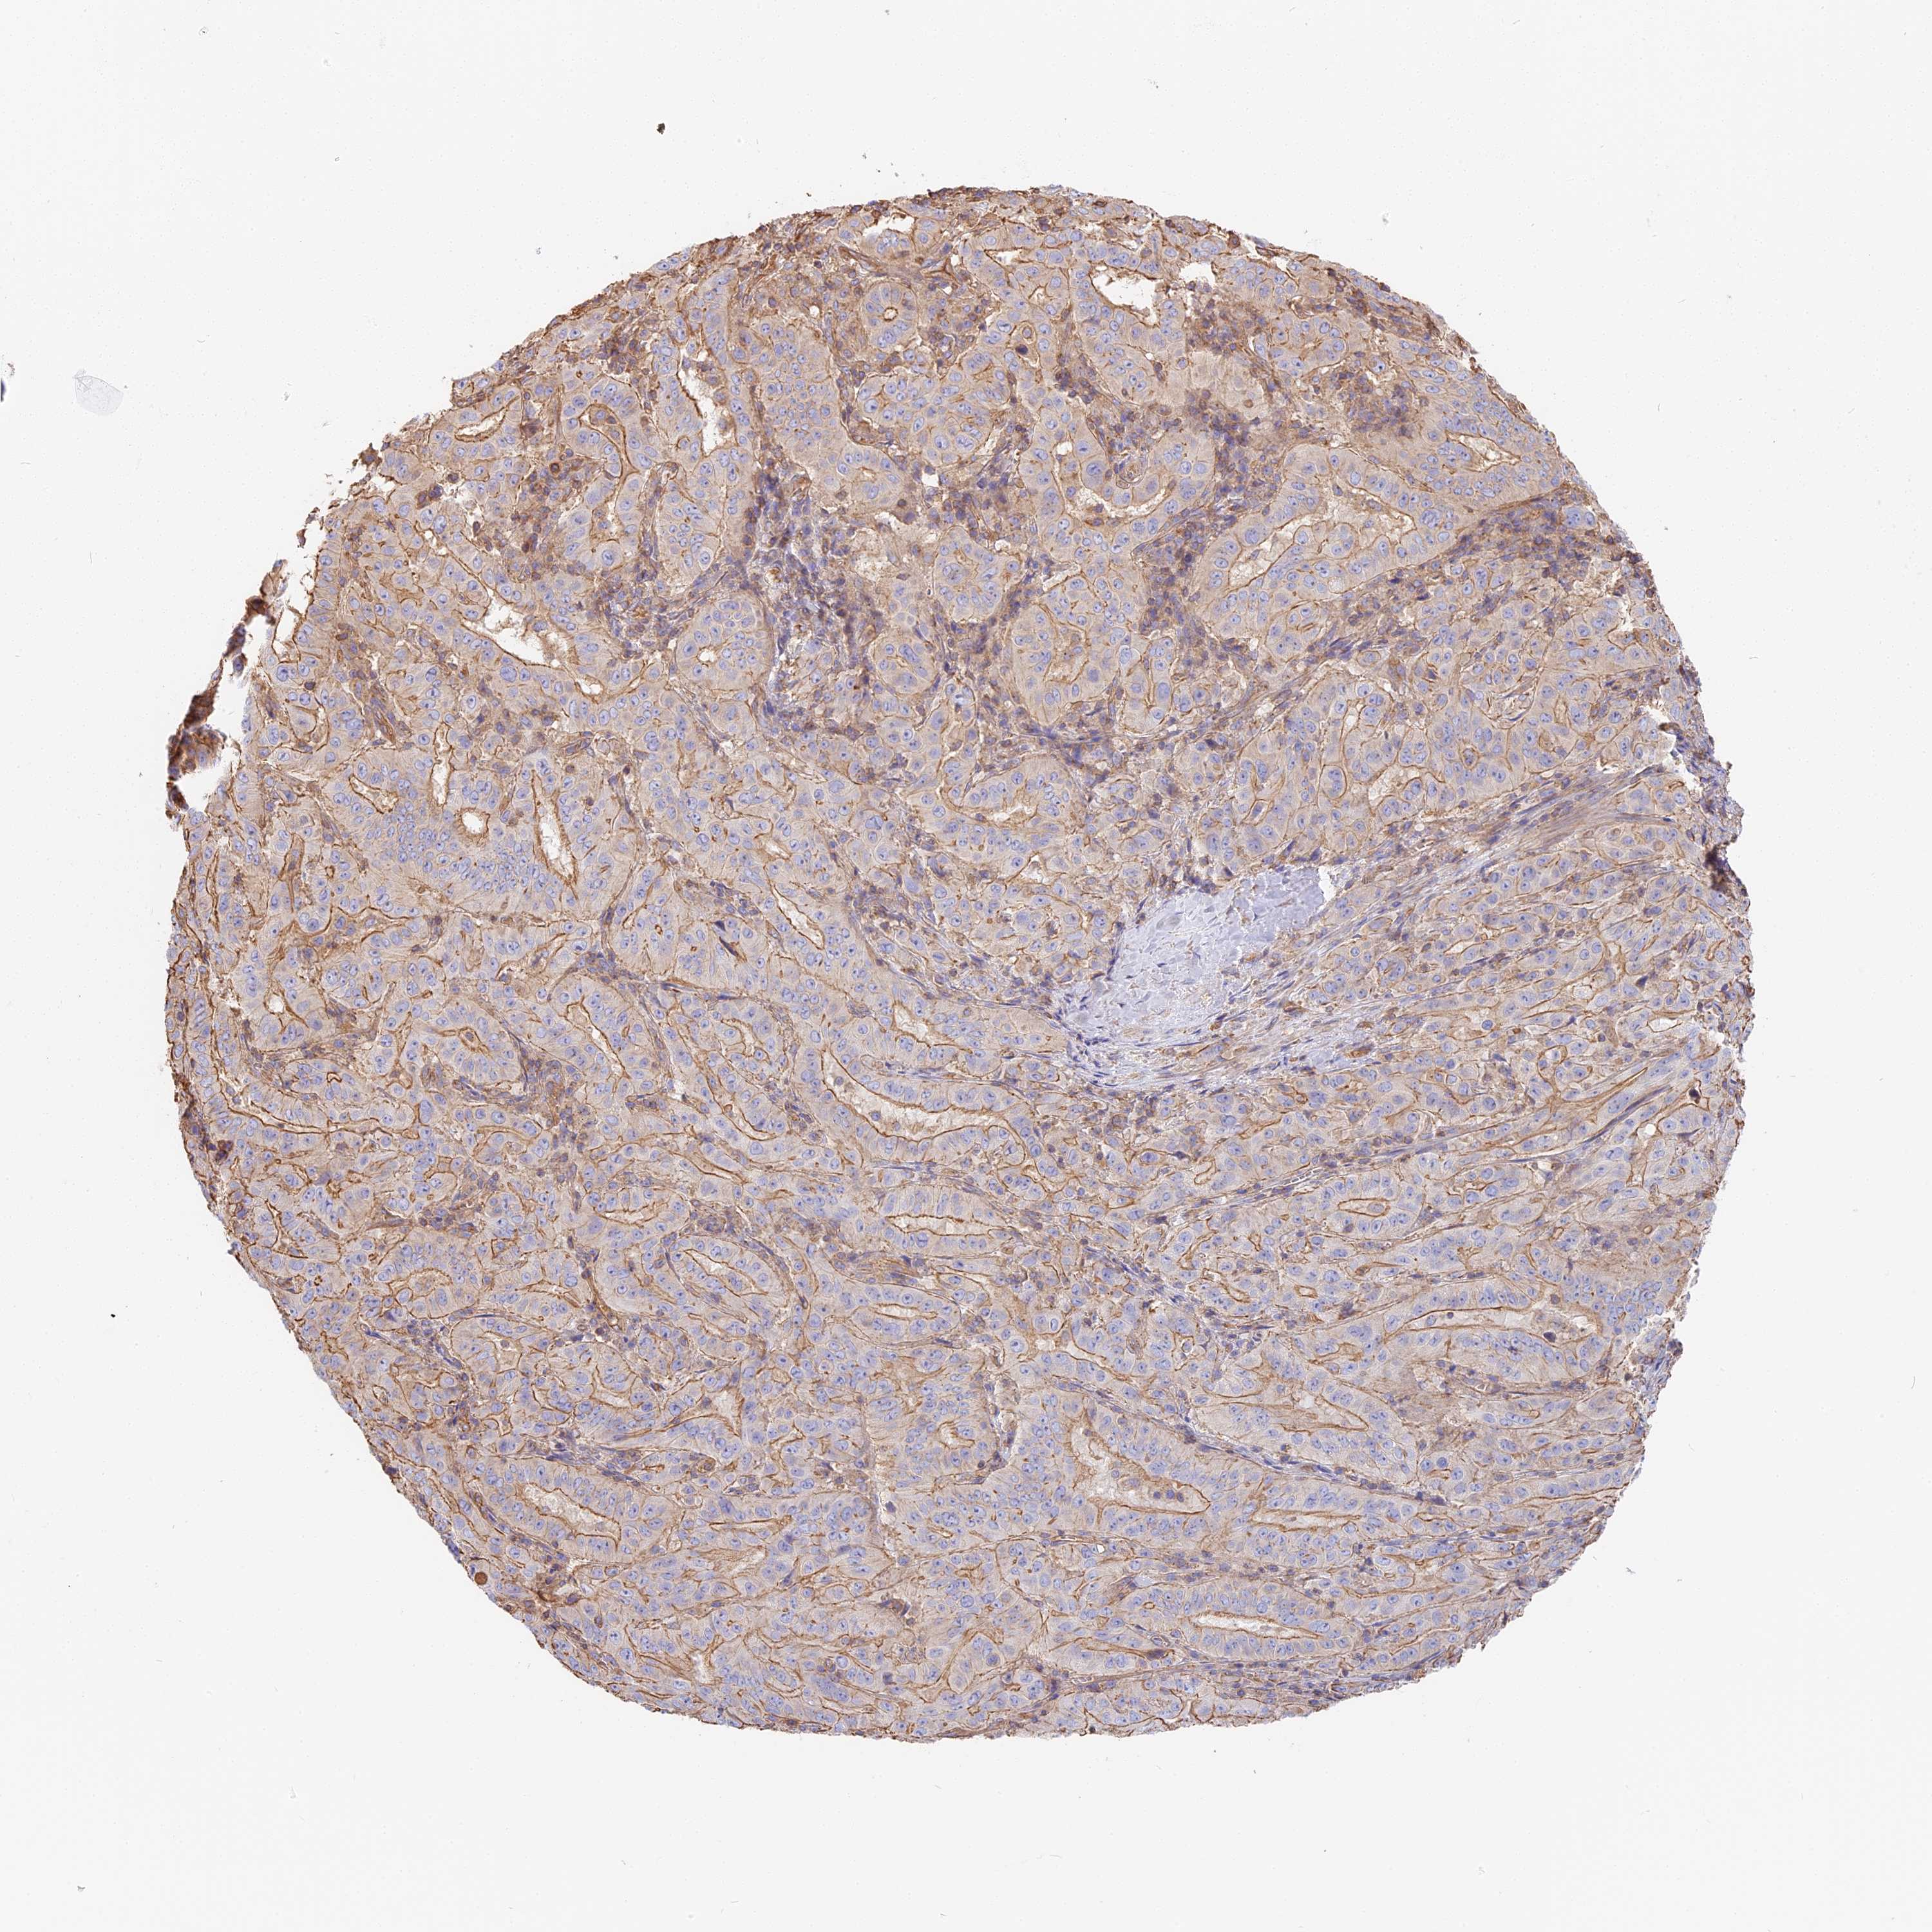

PANCREATIC CANCER - Protein expressioni

A mouse-over function shows sample information and annotation data. Click on an image to view it in a full screen mode. Samples can be filtered based on level of antibody staining by selecting one or several of the following categories: high, medium, low and not detected. The assay and annotation is described here.

Note that samples used for immunohistochemistry by the Human Protein Atlas do not correspond to samples in the TCGA dataset.

Antibody stainingi

Antibody staining in the annotated cell types in the current human tissue is reported as not detected, low, medium, or high, based on conventional immunohistochemistry profiling in selected tissues. This score is based on the combination of the staining intensity and fraction of stained cells.

Each image is clickable and will lead to virtual microscopy that enables deeper exploration of all samples and also displays staining intensity scores, fraction scores and subcellular localization as well as patient and tissue information for each sample.

Antibody HPA040701

Staining

High

Medium

Low

Not detected

Intensity

Strong

Moderate

Weak

Negative

Quantity

>75%

75%-25%

<25%

None

Location

Nuclear

Cytoplasmic/membranous

Cytoplasmic/membranous,nuclear

Adenocarcinoma, NOS